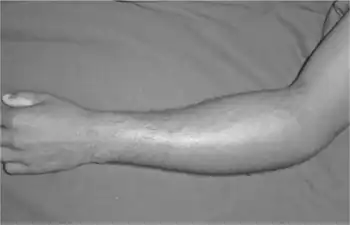

Pyomyositis is a bacterial infection of the skeletal muscles which results in an abscess. Pyomyositis is most common in tropical areas but can also occur in temperate zones.

Pyomyositis is most often caused by the bacterium Staphylococcus aureus.[3] The infection can affect any skeletal muscle, but most often infects the large muscle groups such as the quadriceps or gluteal muscles.[2][4][5]